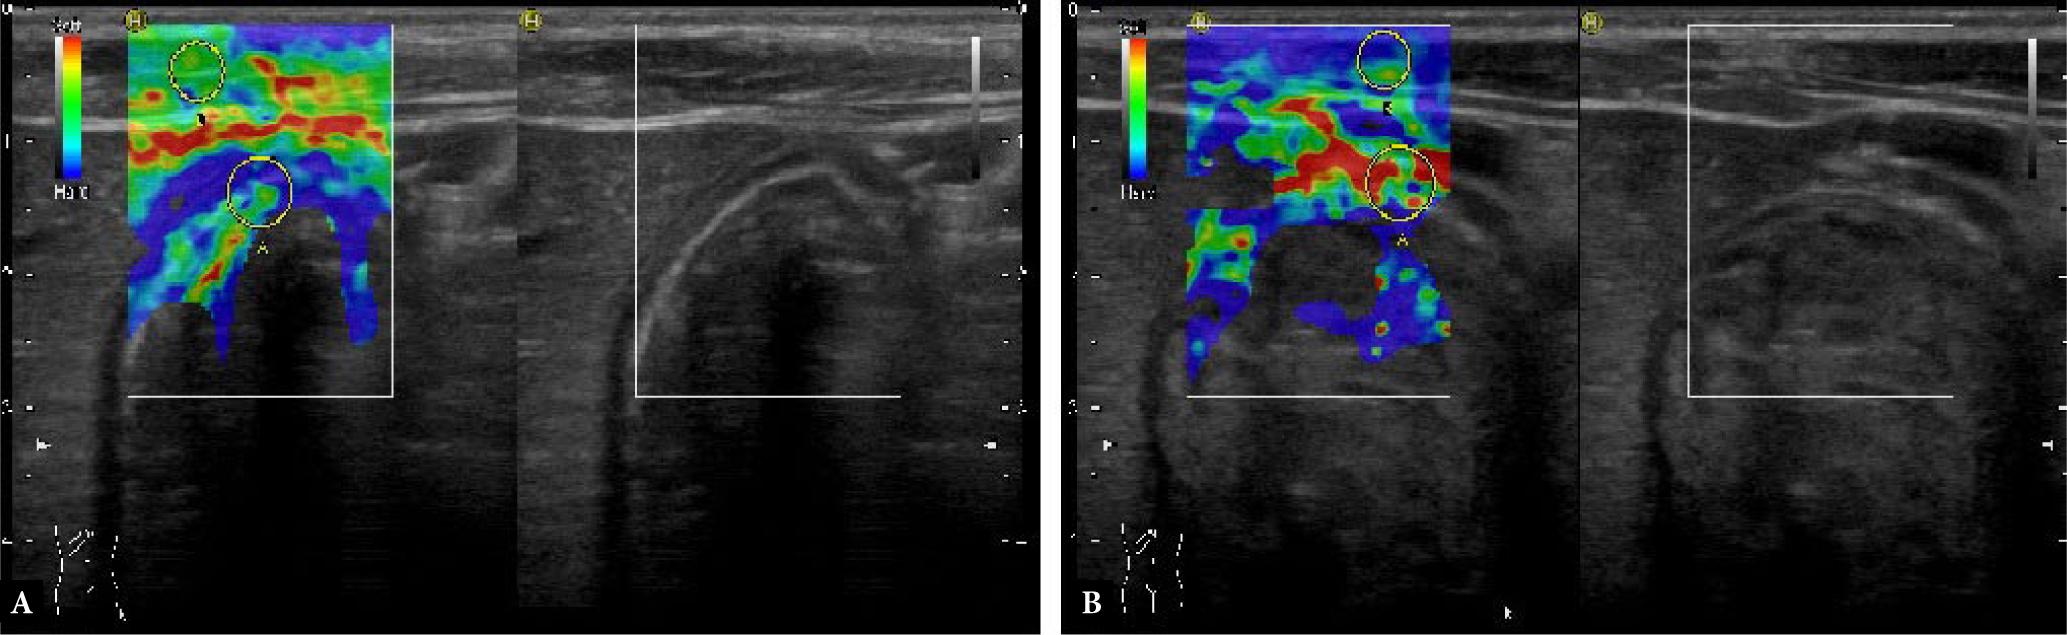

Fig. 1.

A. A seven year-old boy suffering from H. pylori infection underwent strain elastography examination. The strain values obtained from the thickened gastric wall were compared with the stomach surface of the neighboring muscle tissue which was accepted normal. B. Strain value measurement in a healthy 5-year-old volunteer boy. After clinical examination, the patient’s gastric wall was scanned using B-mode sonography and after no thickening has been shown, the color map was obtained and the region of interest was measured. The value was 0.24, which corresponded to normal limits in the healthy volunteer group